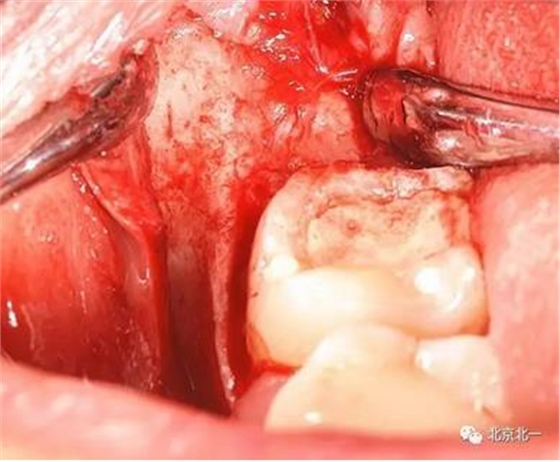

圖六:切開翻瓣, 看見骨面清晰,未見智齒

總結(jié):單純拍片看牙齒并不復(fù)雜, 通過微創(chuàng)拔牙有絲分裂可以避免傷及神經(jīng), 本病例特殊之處在于牙齒顏色和骨顏色無法區(qū)別。導(dǎo)致去骨或者分牙比較茫然, 不可大意,以及磨牙的手感和去骨的手感一致時(shí),兩者不好區(qū)分。 只能偏向保守, 多角度拍片再三確認(rèn)后予以安全拔除。 另外CBCT模式上看智齒位置也有誤差,醫(yī)師要根據(jù)經(jīng)驗(yàn)調(diào)整,特別是在這種哪里是骨,哪里是牙的情況,不能盲目大范圍去骨導(dǎo)致術(shù)中骨折。

另外重點(diǎn):強(qiáng)調(diào)無菌,注意不要污染手術(shù),位置深,創(chuàng)傷大,完全是一個(gè)口腔頜面部手術(shù), 按照外科原則準(zhǔn)備。 該病例手術(shù)后口服消炎藥,并沒有輸液抗炎。 腫脹不明顯和書中完全無菌操作, 用生理鹽水冷卻的專用種植機(jī)分牙,拒絕管路水污染, 無敲擊以及術(shù)后引流片引流有很大關(guān)系。